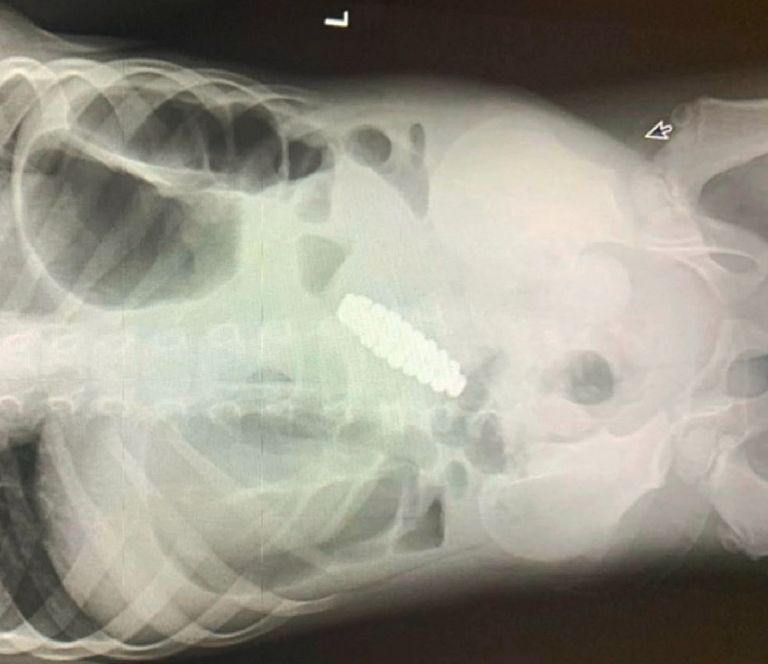

Magazyn medyczny "Journal Of Pediatric Surgery Case Reports" opublikował artykuł, który ukaże się w lutowym wydaniu. Dotyczy on czteroletniego chłopca, który skarżył się przez dwa dni na ból brzucha. Towarzyszyły mu także zaparcia i wymioty.

Kiedy chłopczyk został w końcu zabrany do szpitala, zdiagnozowano u niego ostre zapalenie wyrostka robaczkowego, po czym przeprowadzono operację. Niestety zabieg nie przyniósł oczekiwanego rezultatu, a po trzech dniach czterolatek zaczął wymiotować żółcią.

Nietypowe objawy nie ustępowały, więc lekarze zdecydowali o przeprowadzeniu dodatkowych badań. Wtedy okazało się, że przyczyną bólu jest metalowa bransoletka w brzuchu.

Niestety biżuteria zablokowała jelito chłopca i pokaleczyła jego wnętrze. By zapobiec kolejnym uszkodzeniom, lekarze przeprowadzili pilną laparotomię, usuwając bransoletkę. Składała się z 18. sześciokątnych magnesów.